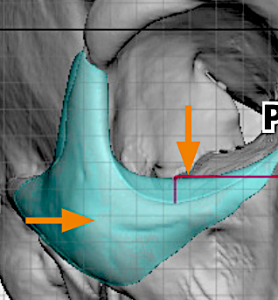

3. Inferior Extension

- Extends below the infraorbital rim while avoiding the infraorbital nerve

- Positioned more laterally relative to the nerve

- Provides vertical support at the lid–cheek junction

- Softens the transition from a negative to a more neutral vector

Thickness Gradient

- Maximum thickness at the infraorbital–cheek junction

- Gradual tapering medially, laterally, and inferiorly

Surgical Access

- Typically placed through a subciliary (lower eyelid) incision, critical for an implant that saddles the rim

- Intraoral access used when significant maxillary extension is required

- Implant design considers insertion pathway

- May be fabricated as a multi-piece design for safe placement